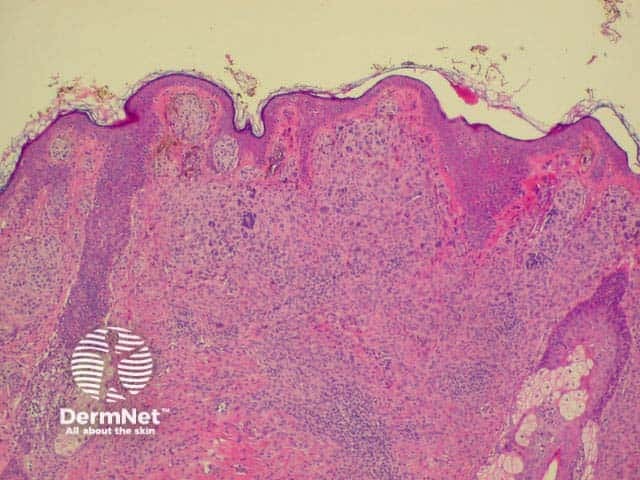

Histology is shown below.

Histology of intradermal naevus  Superficial epithelioid naevus cells  Deeper small dark naevus cells